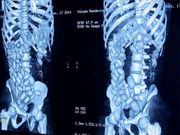

Radiographie d'une mule transportant des boulettes de stupéfiants dans son estomac

Le prévenu, de sexe masculin, a été interpellé au niveau de l’aérogare. Soumis à un test urinaire qui s’est révélé positif, l’interrogatoire l’a finalement conduit à avouer qu’il devait convoyer de la cocaïne confectionnée sous forme de boulettes qu’il aurait ingurgitées. De suite, il a expulsé trois (03) boulettes accusant à la pesée, cent (100) grammes. Acheminé à l’hôpital Principal de Dakar, le 26 mars vers 00 heure 30 minutes, aux fins de subir un examen médical, le rapport provisoire du médecin laisse apparaître que près de trente-deux (32) boulettes resteraient dans son estomac. Ce qui ramènerait le nombre de boulettes ingurgitées par la mule à trente-cinq (35). Le processus d’extraction des boulettes de cocaïne suit son cours.